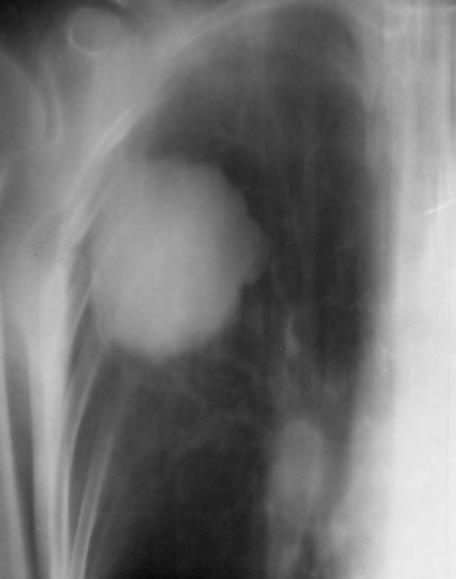

Obr. 1.1 Glioblastom, stav po kraniotomii, CT obraz po i.v. aplikaci kontrastní látky ukazuje heterogenní, expanzivně se chovající útvar s útlakem a přetlakem postranních komor a posunem středočárových struktur. Tvar je nepravidelný – na jednom řezu klamně působí jako multifokální. Rozpadlé centrum je ohraničeno prstenčitou zónou zvýšeného enhancement (hyperdenzity) po aplikaci k.l. i.v. představující oblast nádoru s porušenou hematoencefalickou bariérou –šipka bílá. Okolí útvaru je ovládnuto hypodenzním perifokálním edémem, který však obsahuje nádorové buňky – šipka čárkovaná. Hranice edému představuje prakticky hranici nádoru.

CT nebo MR vyšetření je podstatné vědět, že vnativním zobrazení nemusí být tumor vždy zřetelný, proto je nutné provést vyšetření spoužitím kontrastních látek. Výsledek zobrazovacího vyšetření může svelmi vysokou pravděpodobností informovat opřítomnosti maligního expanzivního ložiska viz obr. 1.1., 1.2., 1.3. Takovýto nález je dostatečnou indikací koperačnímu zákroku. Vdětském věku je možné provést ultrasonografické vyšetření mozku.